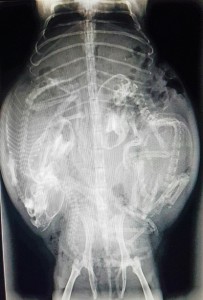

Radiographie de gestation sur une femelle cochon d’inde

Radiographie des 3 petits cochons d’inde dans le ventre de leur maman